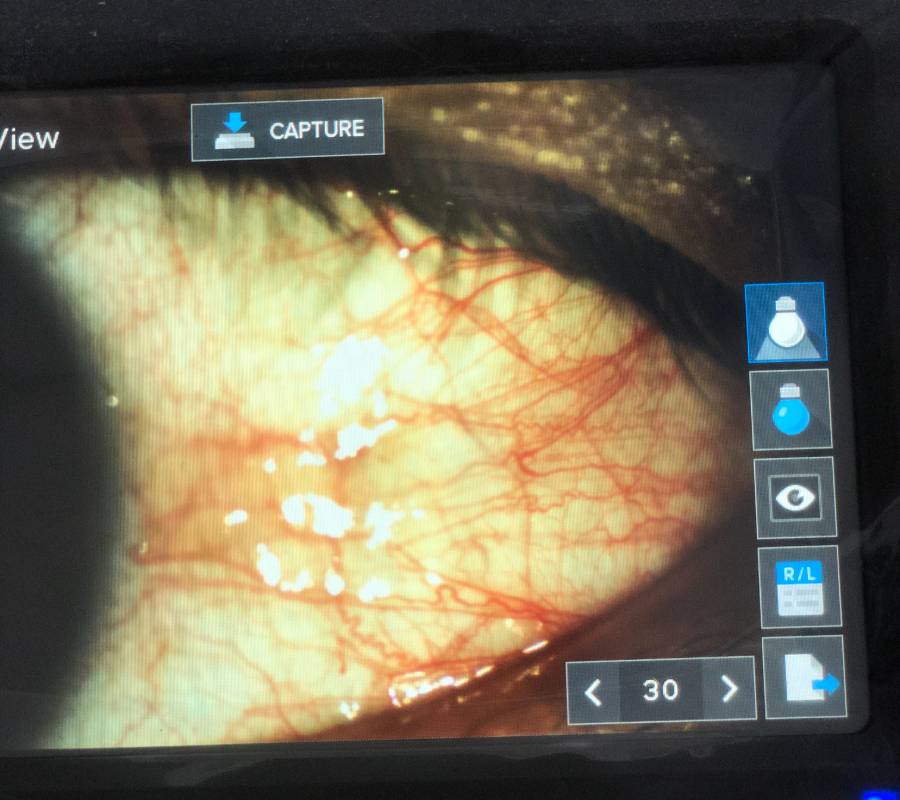

Pemeriksaan menyeluruh ke atas bahagian hadapan (anterior) dan belakang (posterior) mata—termasuk kornea, kanta, iris, retina serta saraf optik.